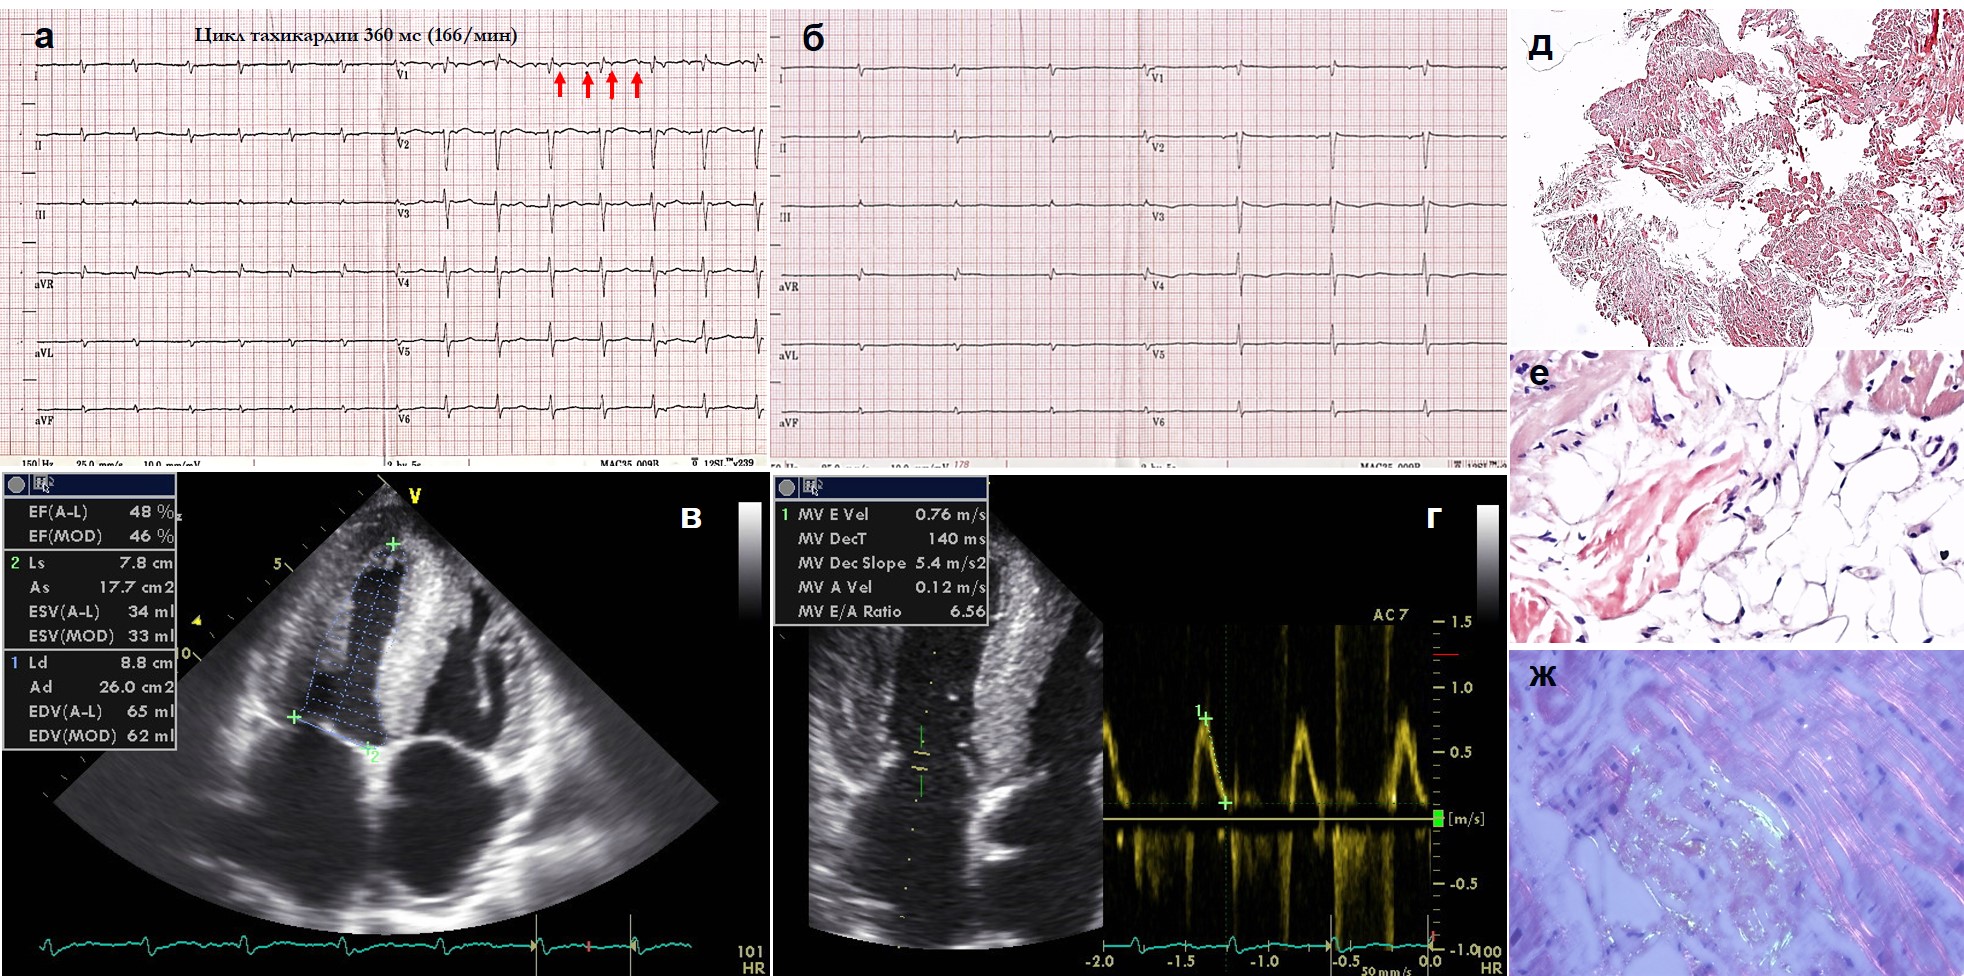

Материал и методы. 5 пациентам 40-79 лет с различными морфо-функциональными вариантами поражения сердца и типичными изменениями на ЭКГ (низкий вольтаж QRS, комплексы QS, недостаточное нарастание зубцов R, отсутствие признаков гипертрофии левого желудочка, ЛЖ) с целью верификации предполагаемого амилоидоза сердца выполнены ЭхоКГ, иммуногистохимическое исследование крови и мочи на легкие цепи иммуноглобулинов, биопсия подкожного жира и слизистой десны/кишки, МСКТ сердца (n=3), МРТ (n=1), сцинтиграфия с 99Тс-пирофосфатом с оценкой через 1 час после введения индикатора (n=1), эндомиокардиальная биопсия (n=2), определение титра антикардиальных антител (n=2), ДНК-диагностика (n=1).

Результаты. Диагноз амилоидоза сердца во всех случаях подтвержден. Его морфо-функциональными вариантами были РКМП с гипертрофией ЛЖ, гипертрофическая кардиомиопатия (ГКМП) без признаков рестрикции, но с прогрессирующим падением фракции выброса (ФВ) ЛЖ, дилатационная кардиомиопатия (ДКМП), выраженная гипертрофия с рестрикцией и низкой ФВ, минимальная гипертрофия без рестрикции и систолической дисфункции. Диагностированы AL-тип (n=2, в одном случае с миопатией, которая имитировала картину “дерматомиозита”), мутантный TTR (n=1, новая мутация Thr40Asn) и дикий TTR (n=2) типы. Ведущими клиническими проявлениями стали бивентрикулярная сердечная недостаточность и предсердные нарушения ритма: устойчивая мерцательная аритмия у 3 больных (одному из них до верификации амилоидоза выполнены РЧ-модификация операции “лабиринт”, истмус-блок без стойкого эффекта) и частая наджелудочковая экстрасистолия еще у одной. Больному с мутантным ATTR имплантирован ИКД с последующей заменой на CRT-D, получен прирост ФВ с 24% до 31% (пациент наблюдается 8 лет). В качестве морфологического эквивалента тяжелой систолической дисфункции у него может рассматриваться отложение амилоида в миокардиальных артериях. МСКТ выявила типичное субэндокардиальное отсроченное накопление у 2 из 3 больных, в одном случае одновременно отмечено диффузное накопление 99Tc-пирофосфата в миокарде. Антитела к ядрам кардиомиоцитов (специфический АНФ) выявлены у больной с AL- типом и ДКМП, что не позволяло исключить миокардит.